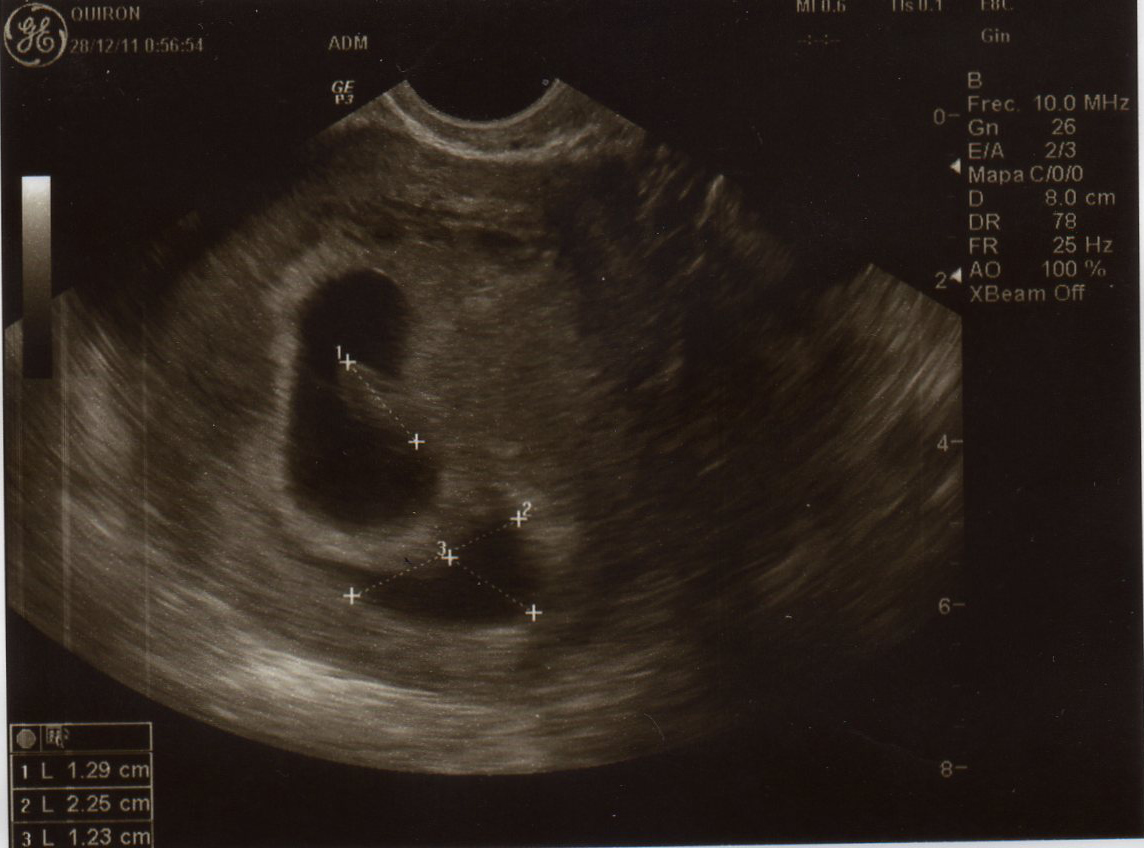

Foro 6 Semanas De Embarazo Y Test Negativo, EMBARAZADA CON PRUEBA NEGATIVA ¿ES POSIBLE, 15.72 MB, 11:27, 276,392, Osiris fonseca, 2019-08-30T02:38:00.000000Z, 3, Ecografia 2D & 4D Embarazo de 6 semanas Clinica Ginecologica Dr. Rafael, www.youtube.com, 1280 x 720, jpeg, WebSi después de confirmarse el embarazo con un test o prueba en sangre positiva, la hormona beta-hCG empieza a disminuir o directamente la prueba de. Web¿Puedo estar de 6 semanas de embarazo y test negativo? Si con anterioridad ya habías tenido un test de embarazo positivo y ahora te da negativa la prueba de embarazo., 20, foro-6-semanas-de-embarazo-y-test-negativo, Novedades y Muebles WebSi después de confirmarse el embarazo con un test o prueba en sangre positiva, la hormona beta-hCG empieza a disminuir o directamente la prueba de. Web¿Puedo estar de 6 semanas de embarazo y test negativo? Si con anterioridad ya habías tenido un test de embarazo positivo y ahora te da negativa la prueba de embarazo.